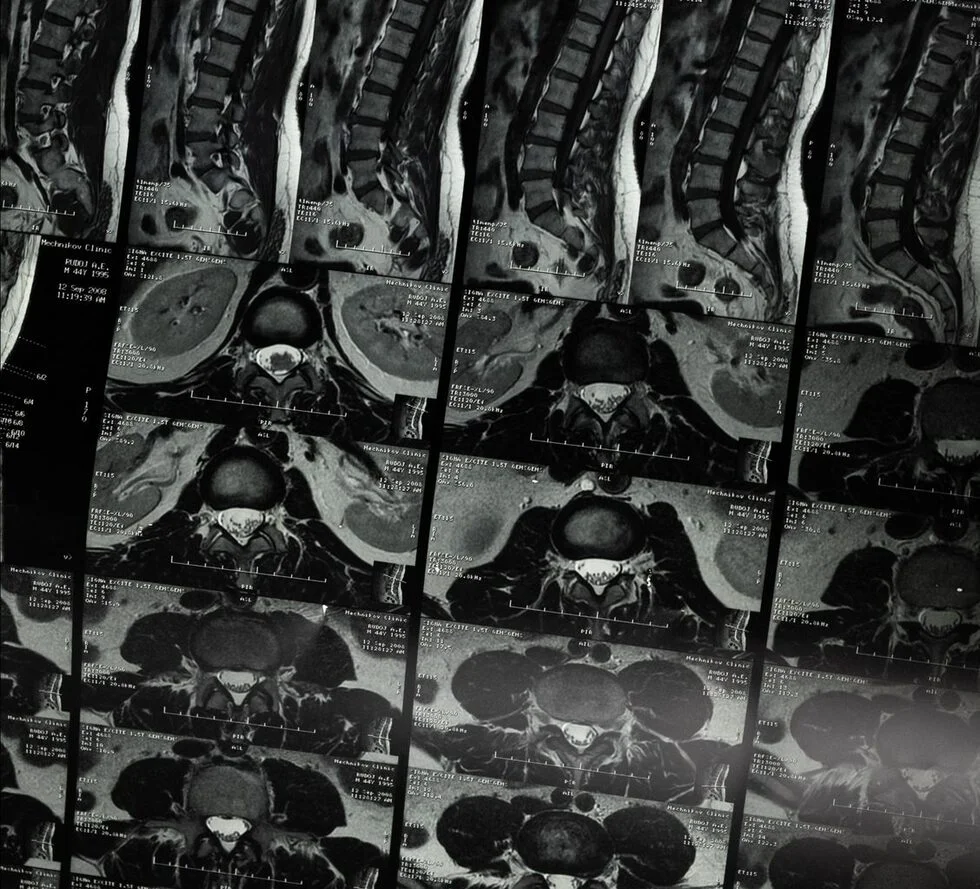

One notable study involved an absorbable biopolymer scaffold placed in the thoracic spine. Early results showed participants regaining partial sensation and movement compared to patients who did not receive the intervention. These outcomes highlight how spinal cord injury clinical trials may transform the future of rehabilitation.

The neuro-spinal scaffold developed by InVivo Therapeutics Corp. represents one of the most promising technologies in the field. This porous device is inserted into the damaged spinal cord, where it gradually dissolves while supporting nerve regeneration.

- Target area: Thoracic spine (T1–T12)

- Purpose: Encourage regrowth and prevent further collapse of injured tissue

- Results: Patients reported improved sensation, reduced complications, and, in some cases, partial mobility gains

Clinical results published in leading journals like Neurosurgery indicate the potential for significant quality-of-life improvements.